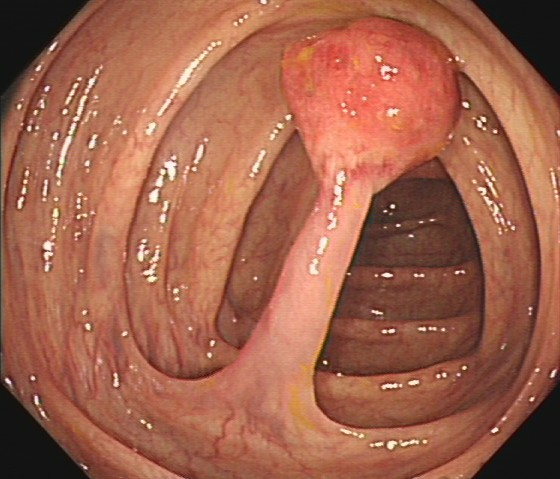

(2)陈先生(44岁,乙状结肠息肉,图2)

图2

病理诊断:(乙状结肠)管状腺瘤,局灶癌变-黏膜内癌(腺癌),脉管未见癌栓,蒂未见累及。

解读:这是从腺瘤发展成癌的典型案例。“局灶癌变”指息肉中只有一小部分区域发生了真正的癌变。“黏膜内癌”指癌细胞仍局限于黏膜层内,尚未穿透黏膜肌层向更深层浸润。脉管无癌栓、蒂部未累及是非常积极的信号,表明癌细胞尚未通过血管/淋巴管扩散,也未侵犯息肉蒂部。此时完整切除息肉,很大可能达到根治效果。距离进展期癌:非常近,但尚属极早期,原位癌/粘膜内癌。